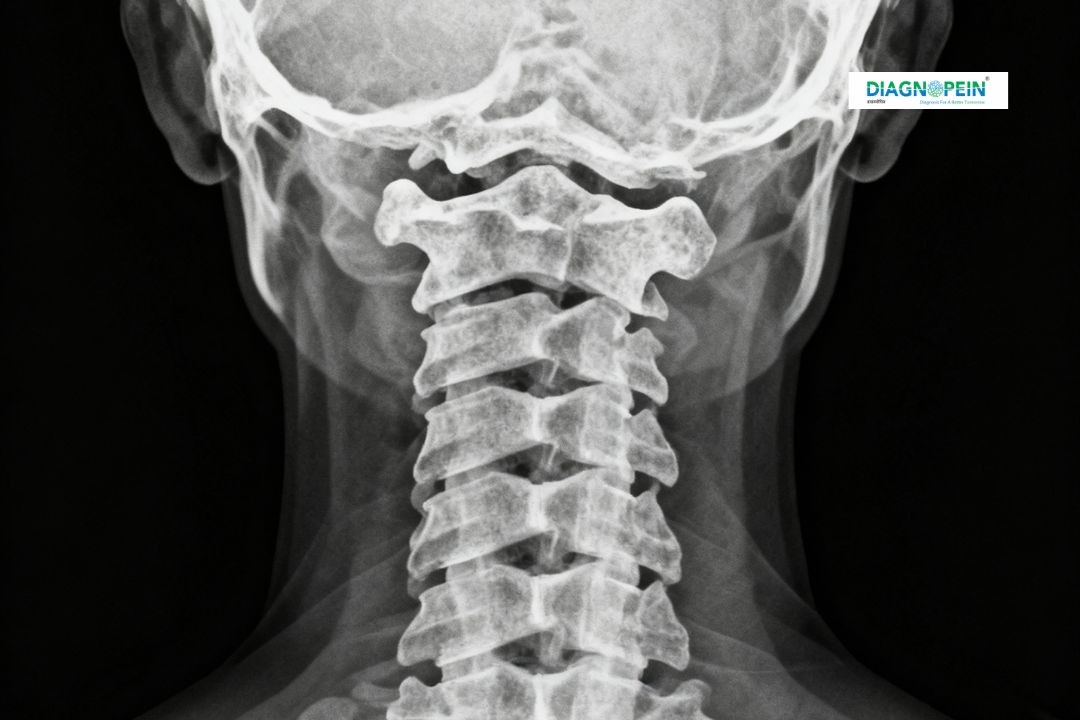

The X-Ray Cervical AP View is a specialized diagnostic imaging test used to capture clear front-to-back images of the cervical spine (neck region). It helps radiologists and doctors assess the alignment, structure, and possible abnormalities in the cervical vertebrae. This X-ray view focuses on identifying bone injuries, degenerative changes, and disc space narrowing that may cause neck pain or restricted movement.

At Diagnopein in Karad, the X-Ray Cervical AP View is performed using advanced digital radiography equipment for precise imaging with minimal radiation exposure.

The cervical spine supports the head and enables neck movements. When pain, stiffness, or trauma occurs, an X-Ray Cervical AP View helps identify the cause quickly. This view is particularly important for diagnosing:

1. Cervical spine fractures

2. Degenerative disc disease

3. Vertebral misalignment or dislocation

4. Cervical spondylosis and arthritis

5. Infections or tumors within the cervical spine

The X-Ray Cervical AP View helps evaluate several key parameters, including:

1. Cervical vertebral alignment

2. Intervertebral disc spaces

3. Bone density and continuity

4. Presence of foreign bodies or lesions

5. Structural integrity after injury or surgery

Radiologists at Diagnopein, Karad, interpret these parameters accurately to help referring physicians diagnose and plan effective treatment.